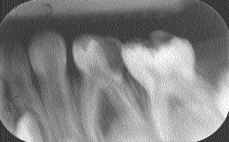

Radiographic Interpretation of Infected Primary Molar Teeth

FIGURE 1--Periapical radiograph tooth 74: radiograph elongated, poor diagnostic quality, apparent distal carious lesion and furcal radiolucency.

By Keith Titley BDS, MScD, FRCD(C), Mark Merryfield DMD, Howard Stein BSc, DDS, MEd. Infected primary molar teeth display radiographic bony changes that are different from those of permanent molars.1 Typically the infection is the result of caries progressing towards the pulp with consequent necrosis and abscess formation. In permanent teeth the infection spreads though … Read more